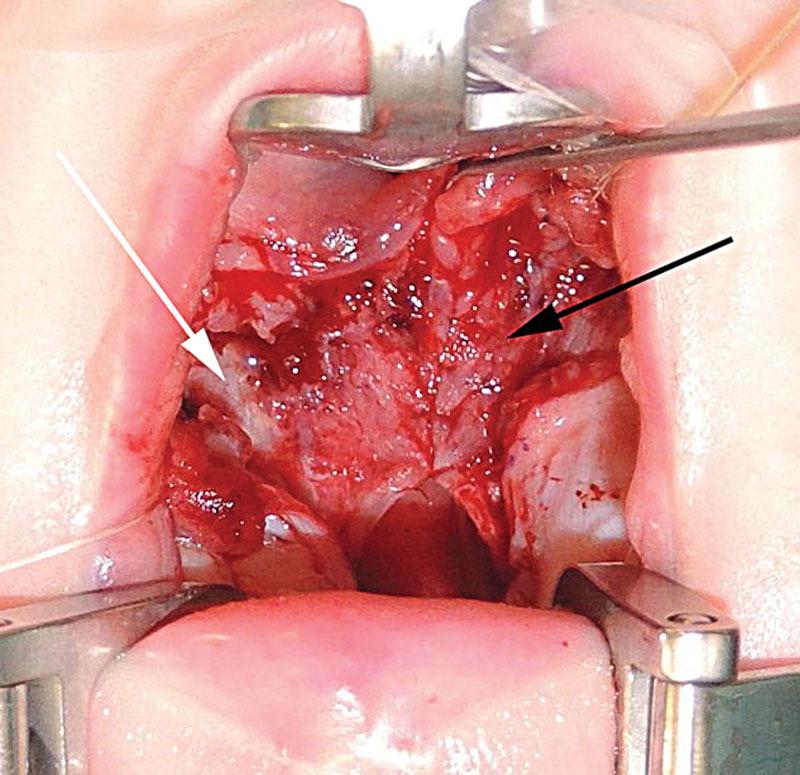

Our aim was to establish a reliable, functional surgical technique for soft palate closure. A step-by-step description of the operative procedure is presented. A cross-over procedure has been developed by combining the principles of a mucosal Z-plasty only on the oral side of the cleft palate, the intravelar veloplasty following Sommerlad's principles and a straight line closure on the nasal side. In the last 2 years, 25 patients have undergone the operation at the Cleft Centre of the 1st Paediatric Department of the Semmelweis University Budapest, Hungary. In all cases the operative technique could be adapted, operations were uneventful and straightforward. This technique was appropriate to close all the soft palate clefts, even the wide ones. This procedure combines the advantages of both procedures and has shown very good early postoperative results.

我们的目标是建立一种可靠的、功能性的软腭闭合手术技术。本文将对手术步骤进行逐步描述。通过结合仅在腭裂口腔侧进行黏膜Z成形术的原则、遵循Sommerlad原则的腭内肌成形术以及在鼻侧进行直线闭合的原则,开发出了一种交叉手术方法。在过去两年中,匈牙利布达佩斯塞梅尔维斯大学第一儿科系腭裂中心有25例患者接受了该手术。在所有病例中,手术技术均可适用,手术过程顺利且简单。该技术适用于闭合所有软腭裂,即使是较宽的腭裂。此手术方法结合了两种手术的优点,术后早期效果非常好。